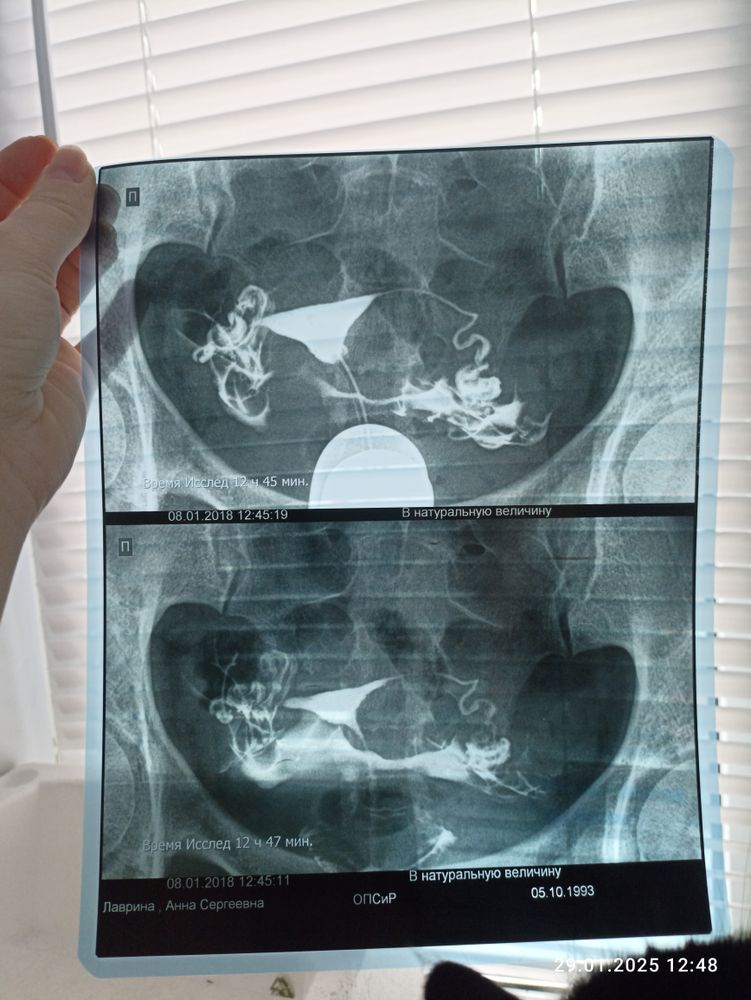

ГСГ и возможность зачатия

Зависит от того сколько вы уже планируете. Трубы у вас очень длинные и извилистые, не трубы, а лабиринты. Если больше года уже не можете забеременеть, то я бы посоветовала ЭКО.

Я про длинные и извитые трубы слышала, что могут быть нефункциональными. У самой такие, естественной беременности не было, правда еще мужской фактор присутствует. Если бесплодие 8 лет то инсеминацию смысла мало